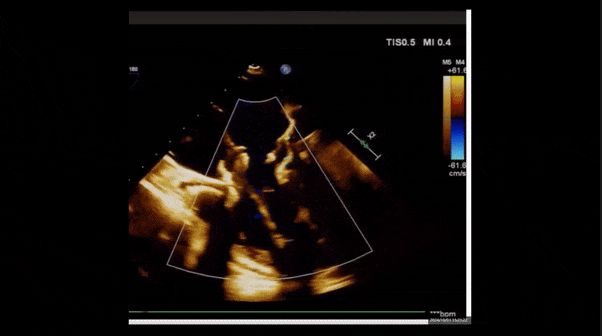

術(shù)前TEE評(píng)估

1、3D TEE顯示雙房及右室擴(kuò)大,右室中段直徑40mm,右室FCA 52%。三尖瓣環(huán)TAPSE 22mm,三尖瓣環(huán)左右徑49mm,三尖瓣隔葉長(zhǎng)度16mm,前葉長(zhǎng)度21mm,后葉長(zhǎng)度34mm,三尖瓣前隔gap 11mm,后隔gap 5.6mm,AP gap 12mm,診斷極重度功能性三尖瓣返流(Type I型三尖瓣:Torrential FTR 5+)。

2、彩色多普勒顯示:收縮期三尖瓣口返流束起源于后隔交界、前后葉之間及前隔交界,返流束縮流頸最大寬度27mm,三尖瓣返流口EOA=2.02cm2,返流容積124ml,收縮期三尖瓣返流峰值速度2.64m/s,返流峰值壓差28mmHg,PAPs 43mmHg,舒張期三尖瓣口平均跨瓣壓差1mmHg,肝左靜脈可見(jiàn)明顯逆向血流波。